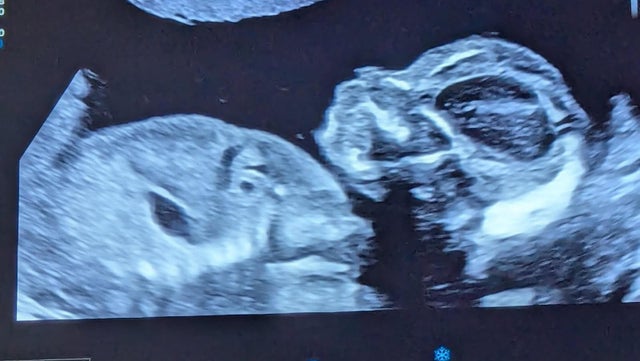

When Sarah and Michael Oliveri went to their 20-week ultrasound for their third pregnancy, they thought to knew what to expect. Their previous visit had been stressful — doctors had detected an abnormality at 16 weeks — but a blood test came back clear. They believed the 20-week scan, taken in August 2024, would continue to show everything was fine.

But as the ultrasound went on, doctors "kept kind of going over the heart," Sarah Oliveri told CBS News.

"They told me in that room that there could potentially be something wrong, and they were sending me down the hall to the cardiology department," she said.

Sarah Oliveri said she and her husband went to the cardiology department "nervous," but trusting their doctors to provide care. When they met the cardiologist, they were told their unborn child had a heart block. It was a condition they had never heard of before.